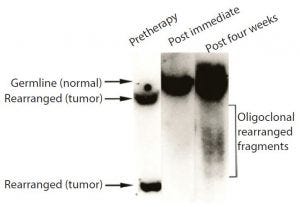

Figure 3: Samples of bone marrow taken before treatment, probed for the characteristic gene of the tumor cells; before treatment, sample contained only tumor cells. By contrast, none of the tumor cell DNA could be detected in a sample taken shortly after Campath treatment.

When we evaluated the recovering cells (which came back after more than a month), they were healthy (Figure 3). We observed same with the bone marrow and no signs of tumor cells, as was the case with Campath-1M and Campath- 1G.